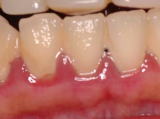

中等度歯周炎

歯周ポケットが4~6mmで、歯槽骨の破壊(歯を支えている顎の骨がとかされている)が起こっている状態。

歯や歯根には、多量のプラークや歯石が付着しています。歯ぐきの腫れ、出血、排膿を伴います。力をかけると、歯が動揺します。

中等度歯周炎の症例です。歯ぐきが赤く腫れ、多量の歯石を認めます。力をかけると歯が動揺します。

細菌が歯槽骨まで侵入し、歯槽骨の破壊が起こっています。